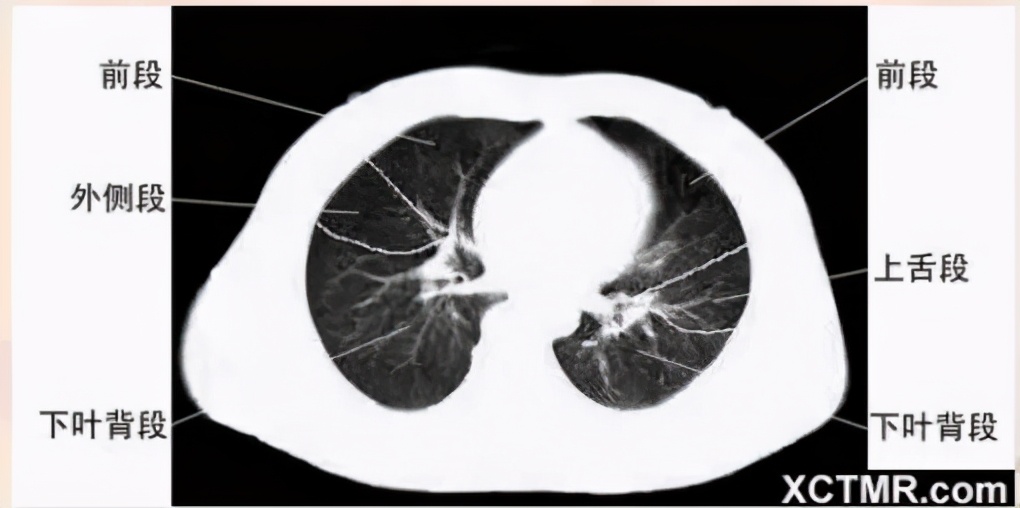

肺段划分